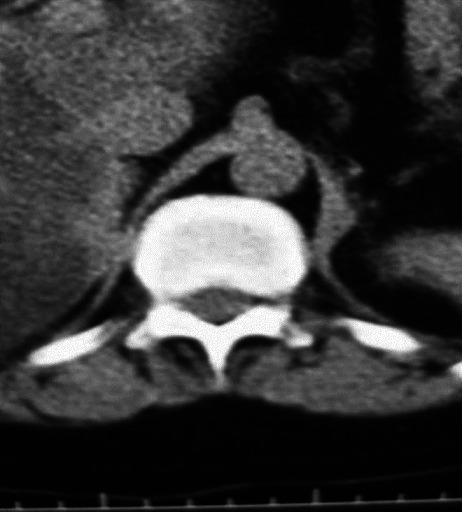

A difficult to treat case of Cushing's syndrome.

https://cdn.ncbi.nlm.nih.gov/pmc/blobs/c06b/3659896/1f52d0711881/IJEM-17-181-g001.jpg